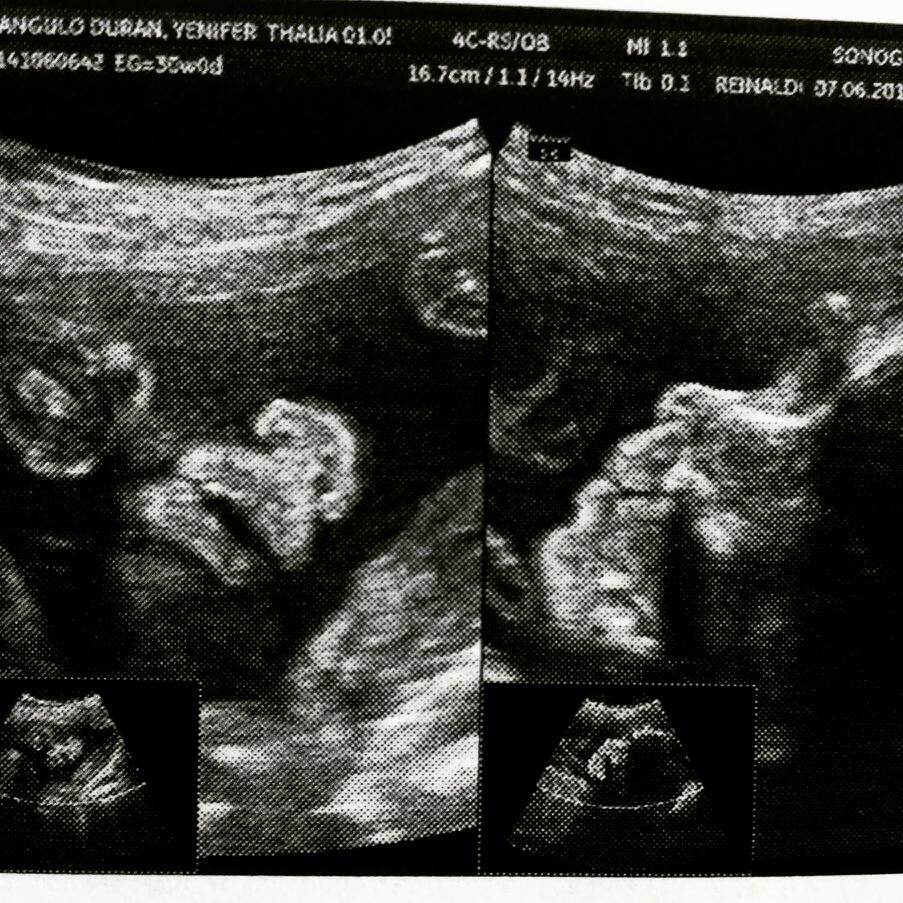

Hola manita, soy thalia mama por.primera vez de 22 años. tengo aproximadamente 32 semanas de embarazo me encuentro en bogota pero soy venezolana estaba viviendo en ecuador y decid. Regresar a Venezuela a dar a luz a mi beba, pero se me complicó ya que estoy dilatando y me mandaron reposo. Quiero saber si en mi condición puedo viajar en avión y Ps si no me toca dar a luz aqui Lejos de mi familia y la verdad nose como quedaría el registro de mi niña eso me tiene algo estresada que.me.dicen ustedes mamitas